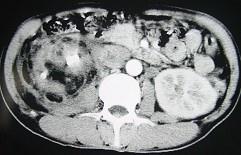

问题 女,43岁,右腰部疼痛不适2年余,加重3天,CT及MR检查如图,应诊断为 ( )

选项 A、右肾脂肪肉瘤 B、右肾海绵状血管瘤 C、右肾错构瘤合并出血 D、右肾脂肪瘤 E、右肾癌

答案 C